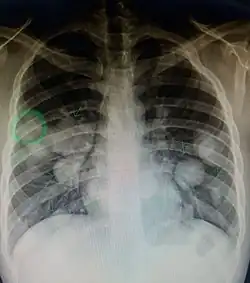

Pulmonary metastases shown on Chest X-Ray

The cells in a metastatic tumor resemble those in the primary tumor. Once the cancerous tissue is examined under a microscope to determine the cell type, a doctor can usually tell whether that type of cell is normally found in the part of the body from which the tissue sample was taken.